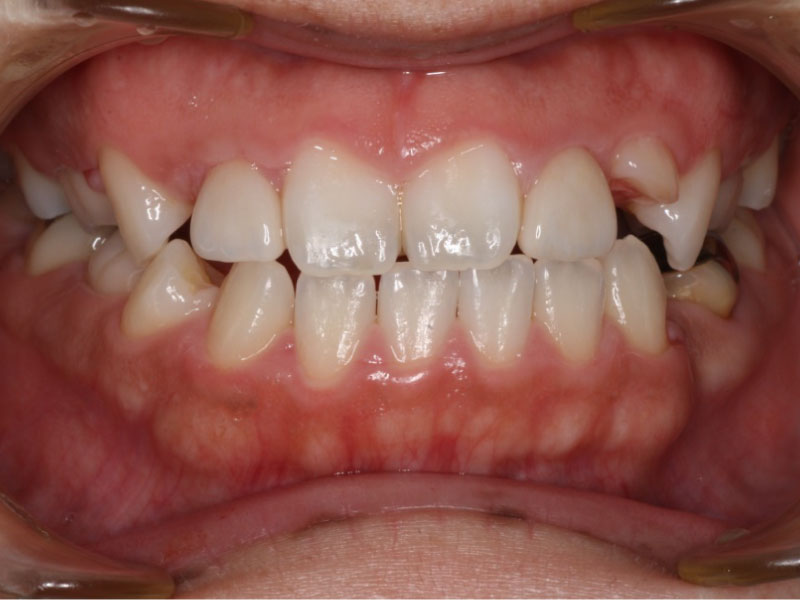

after

before

経過